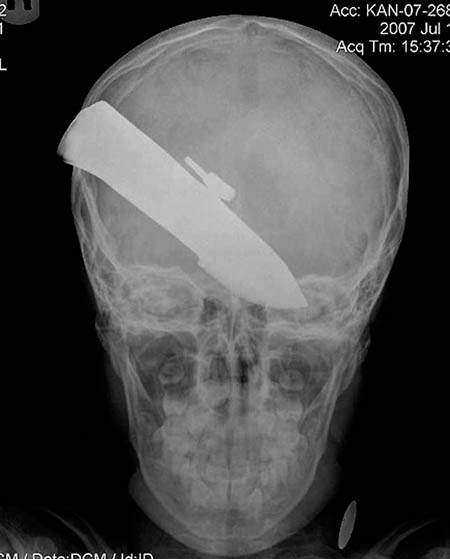

10歲少年的頭被刀子穿過

圖片來自:http://www.po-kaki-to.com/